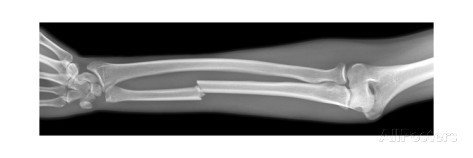

Radiography

(X-Rays)

- Uses ionizing radiation

How does it work?

- X-ray beam passed through the body

- Portion of the beam is scattered or absorbed by bones, organs, etc.

- Remaining pattern is transmitted to a detector for further processing as a picture

- Useful for detecting bone problems, infection, and tumors